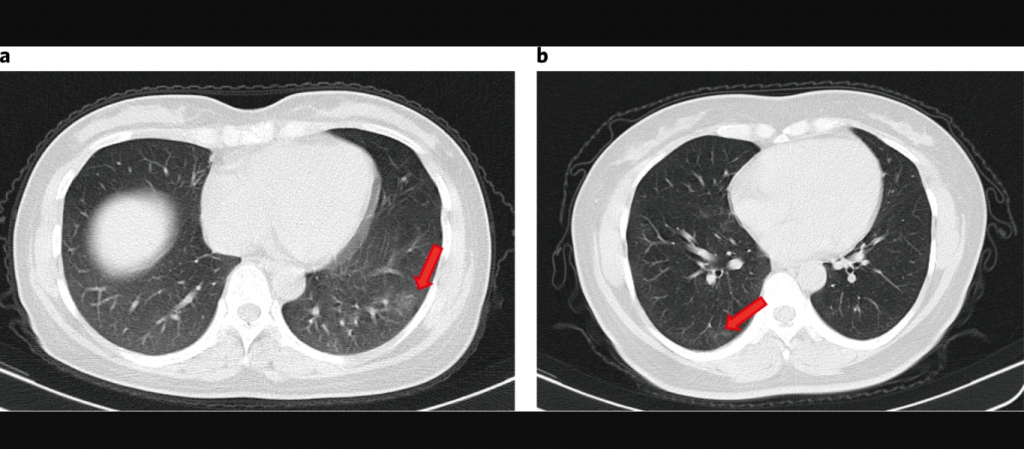

Gráfica: Tórax de dos pacientes asintomáticos

Otra gran incógnita son los pacientes que dan positivo al Covid-19, pero que no presentan síntomas. Se calcula que estos representan el 40% de las personas infectadas. Luego, hay una parte que presenta síntomas leves, que pueden permanecer en el domicilio, mientras que otra desarrolla una enfermedad severa, requiriendo oxígeno y hospitalización.

“De los asintomáticos no sabemos nada. La producción de anticuerpos sería más baja. Pero por otro lado, hay estudios recientes que muestran que un tipo de células, los linfocitos T, tendrían un rol muy importante en la respuesta contra el virus”, dice la académica.